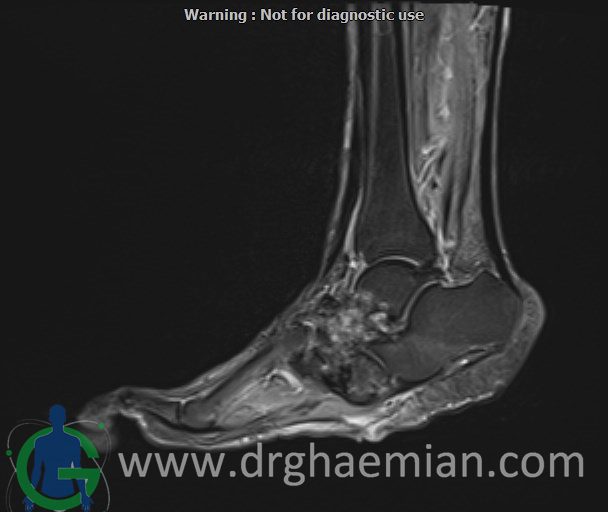

ام آر آی کف پا و انگشتان یک روش تصویربرداری پزشکی است که با استفاده از میدانهای مغناطیسی قوی و امواج رادیویی تصاویر دقیق و باکیفیتی از ساختارهای داخلی کف پا و انگشتان ایجاد میکند. این روش بدون استفاده از اشعههای مضر مانند اشعه ایکس انجام میشود و به پزشک کمک میکند تا با جزئیات بیشتری آسیبها، التهابها یا مشکلات دیگر را تشخیص دهد.در ان کیس یک پای بیمار مبتلا بهب بیماری دیابت دیده میشود.

MRI OF RIGHT FOOT

1.5 Tesla MR System

Multislice, multiplanar and multisequence MR images findings:

There is a skin ulcer in the plantar aspect of the foot, superficial to the midfoot, without obvious collection.

Destruction and erosion of the midfoot structures and articular spaces are seen, resulting in midfoot collapse.

T1 signal intensity of bone marrow in the midfoot region is preserved, and there is no imaging evidence of acute osteomyelitis; however, chronic osteomyelitis cannot be ruled out.

Abnormal high T2WI and low T1WI signal intensity are observed in the 5th proximal and distal phalanges, in association with a suspicious plantar site ulcer, highly suggestive of osteomyelitis in this area.

Other bones, joints, and soft tissues of the foot appear unremarkable.

Impression:

Plantar skin ulcer overlying the midfoot with no associated collection

Structural destruction and erosion of midfoot bones and articular spaces causing midfoot collapse, without definite signs of acute osteomyelitis, though chronic osteomyelitis cannot be excluded

Abnormal marrow signal changes in the 5th proximal and distal phalanges in association with a suspicious plantar ulcer, highly suggestive of osteomyelitis

No other abnormality detected